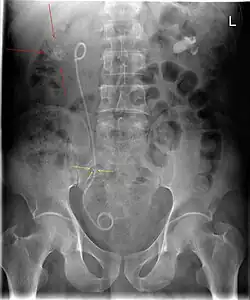

Röntgenbild des Bauchraums mit einliegender Doppel-J-Schiene bei sichtbaren, krankhaften Nierensteinen

Röntgenbild des Bauchraums mit einliegender Doppel-J-Schiene im rechten Harnleiter. Nierensteine im Nierenbecken (rote Pfeile) und im Harnleiter (gelbe Pfeile), wo die Urinabflusshinderung die Harnleiterschienung nach sich zog.